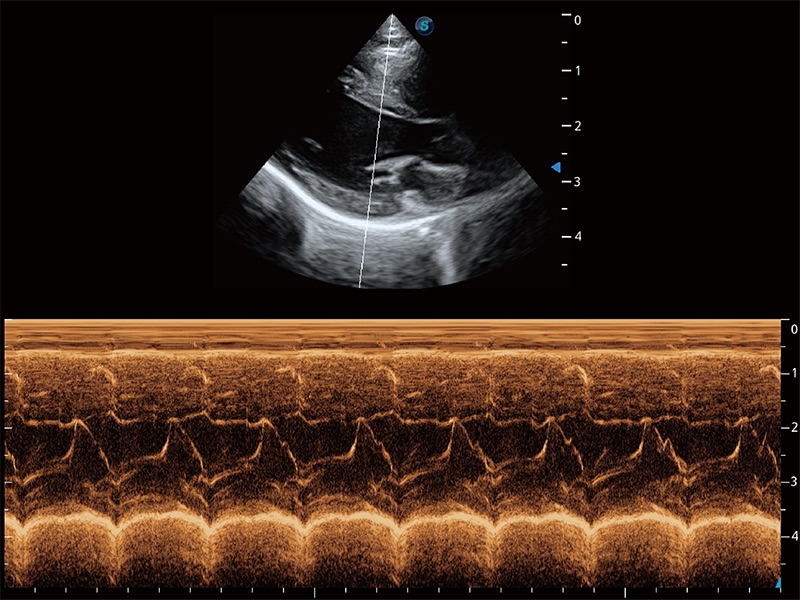

ProPet 80 配备了丰富的心脏探头群、先进的成像技术和专业的心脏测量工具,可帮助动物医生为不同体型和生理结构的动物提供心脏和心肌功能的全面评估。

实时用颜色表示心肌组织运动,观察和定量组织的运动情況,对快速检测与评估心肌的灌注和活性、电传导及心肌收缩和舒张功能等均能提供重要的诊断信息。

通过360度任意调节3条M型取样线,在同一心动周期上观察心脏不同位置的运动曲线,得到准确的心功能测量数据,有效评估心肌运动及左心室功能。